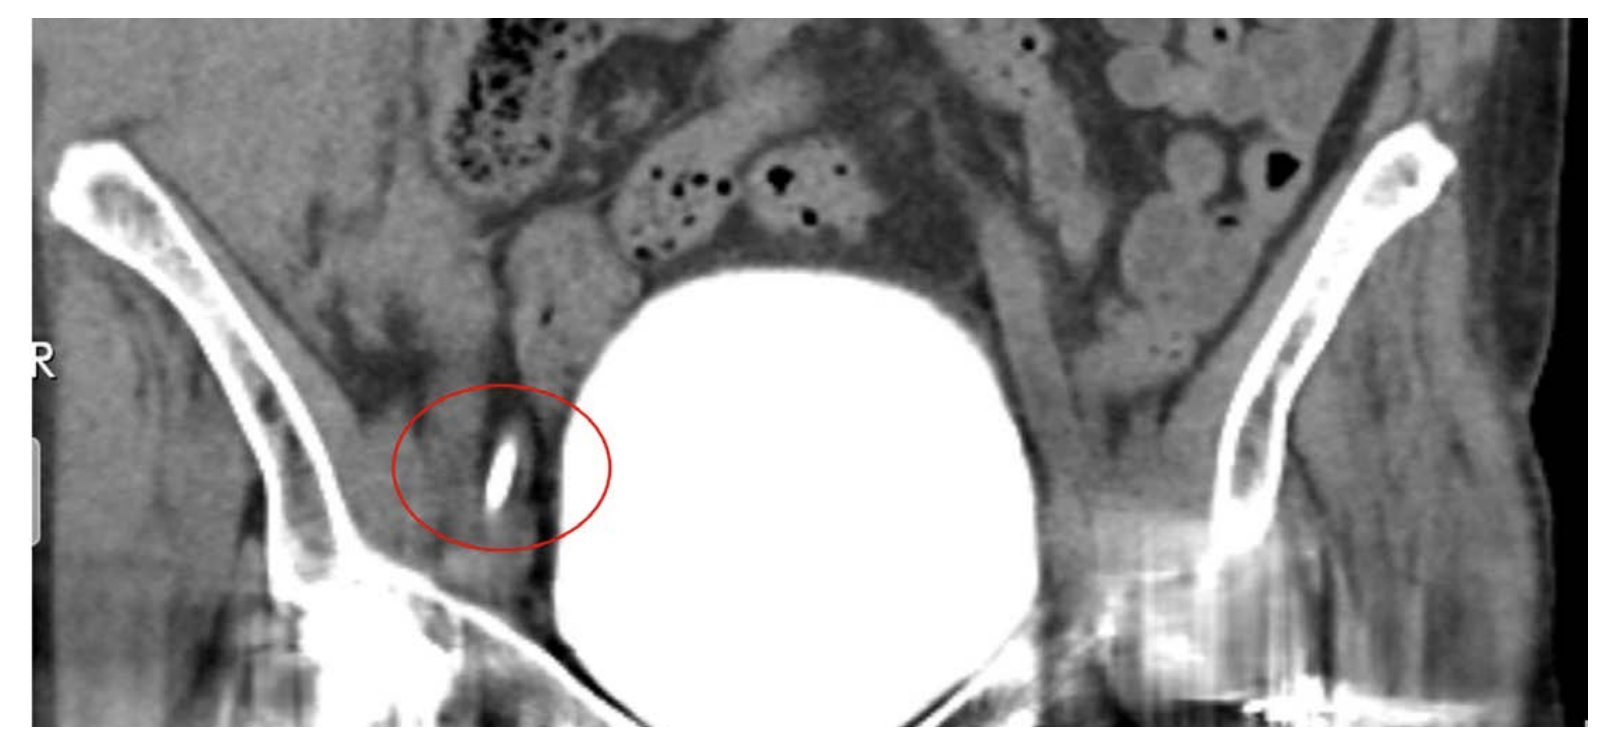

Urgent abdominal CT scan was obtained and revealed a 21 cm right anterolateral abdominal wall intramuscular hematoma that extended to the level of the pelvis with a smaller hematoma in the right groin surrounding the femoral line (Figure 2). The patient was taken back to the catheterization lab and using the retained right common femoral sheath in place, repeat angiography with digital subtraction revealed perforation of a distal branch of the right superficial iliac artery (Figure 3).